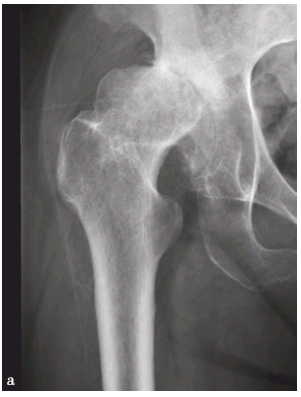

右侧髋臼发育不良伴退行性骨关节病

a.右髋正位片,示右髋臼变浅,髋顶变短,Sharp角增大,股骨头外翻并外上方移位,间隙变窄,髋臼缘骨质增生硬化,股骨头周围骨质增生;

髋臼发育浅小或浅平,顶唇短小,髋臼覆盖率降低,中心边缘角(CE角)减小。股骨颈干角增大,股骨头的负重点外移,髋关节的内侧间隙加宽,关节呈半脱位或全脱位。髋臼顶外侧缘骨质发育不良,臼盖嘴消失,臼盖白线呈外高内低之斜线,Sharp角增大。髋臼边缘增生硬化,股骨头及髋臼软骨下可见假囊肿,股骨头及髋臼边缘可见骨质增生。